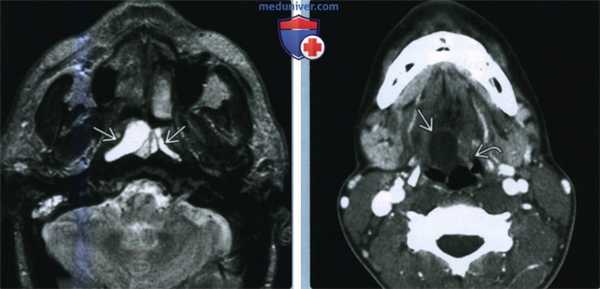

(Слева) При МРТ Т2ВИ в аксиальной проекции с обеих сторон визуализируются ретенционные кисты носоглотки, правая киста крупнее. Обратите внимание, что небольшая левая киста является многодольчатой. Правый сосцевидный отросток частично затемнен.

(Справа) КТ с КУ аксиальный срез на уровне корня языка. Ретенционная киста правой валлекулы у взрослого пациента. Левая валлекула частично заполнена лимфоидной тка -нью язычной миндалины, которая накапливает контраст. Киста щитоязычного протока слепого отверстия располагалась бы ближе к средней линии и не занимала бы валлекулу.